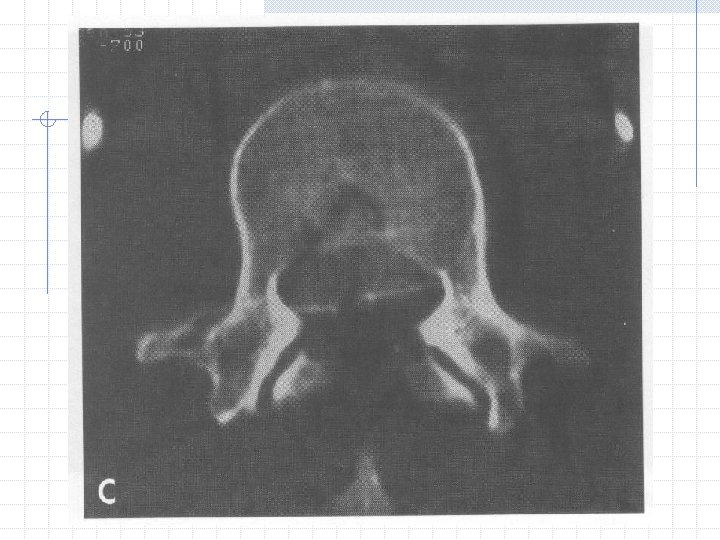

Radiographic Evaluation CT n All cases of suspected injury to posterior elements or posterior vertebral body

Spinal Stability Denis 1983 CT Scan 3 column theory

Burst Fracture Failure of anterior and middle column n Axial compression +/- failure of posterior column n Compression or tensile force Most common at T/L junction